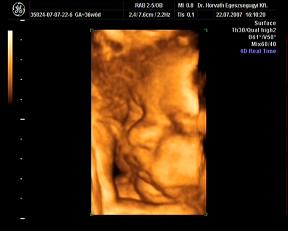

ma megvolt a -ha minden igaz- utolsó ultrahang. Nagyon jó volt, kisit furcsa érzés, hogy Ákossal már nem megyünk ilyenre...de nemsokára gyönyörködhetek benne állandóan 4D-ben-hanggal:D:D:D

Nagyon jól van, hála Istennek, csinált adoki flowmetriát is-az is rendben teljesen. A súlya 2870 gramm-ideális, a méretei a korának megfelelőek. A doki azt mondta, úy készüljek, hogy maximum két hétvégém van még az Urammal kettesben:D:D:D Nagyon várom már!!

Rakok náhény képet:

édes kis grimaszai vannak, nem? :oops: